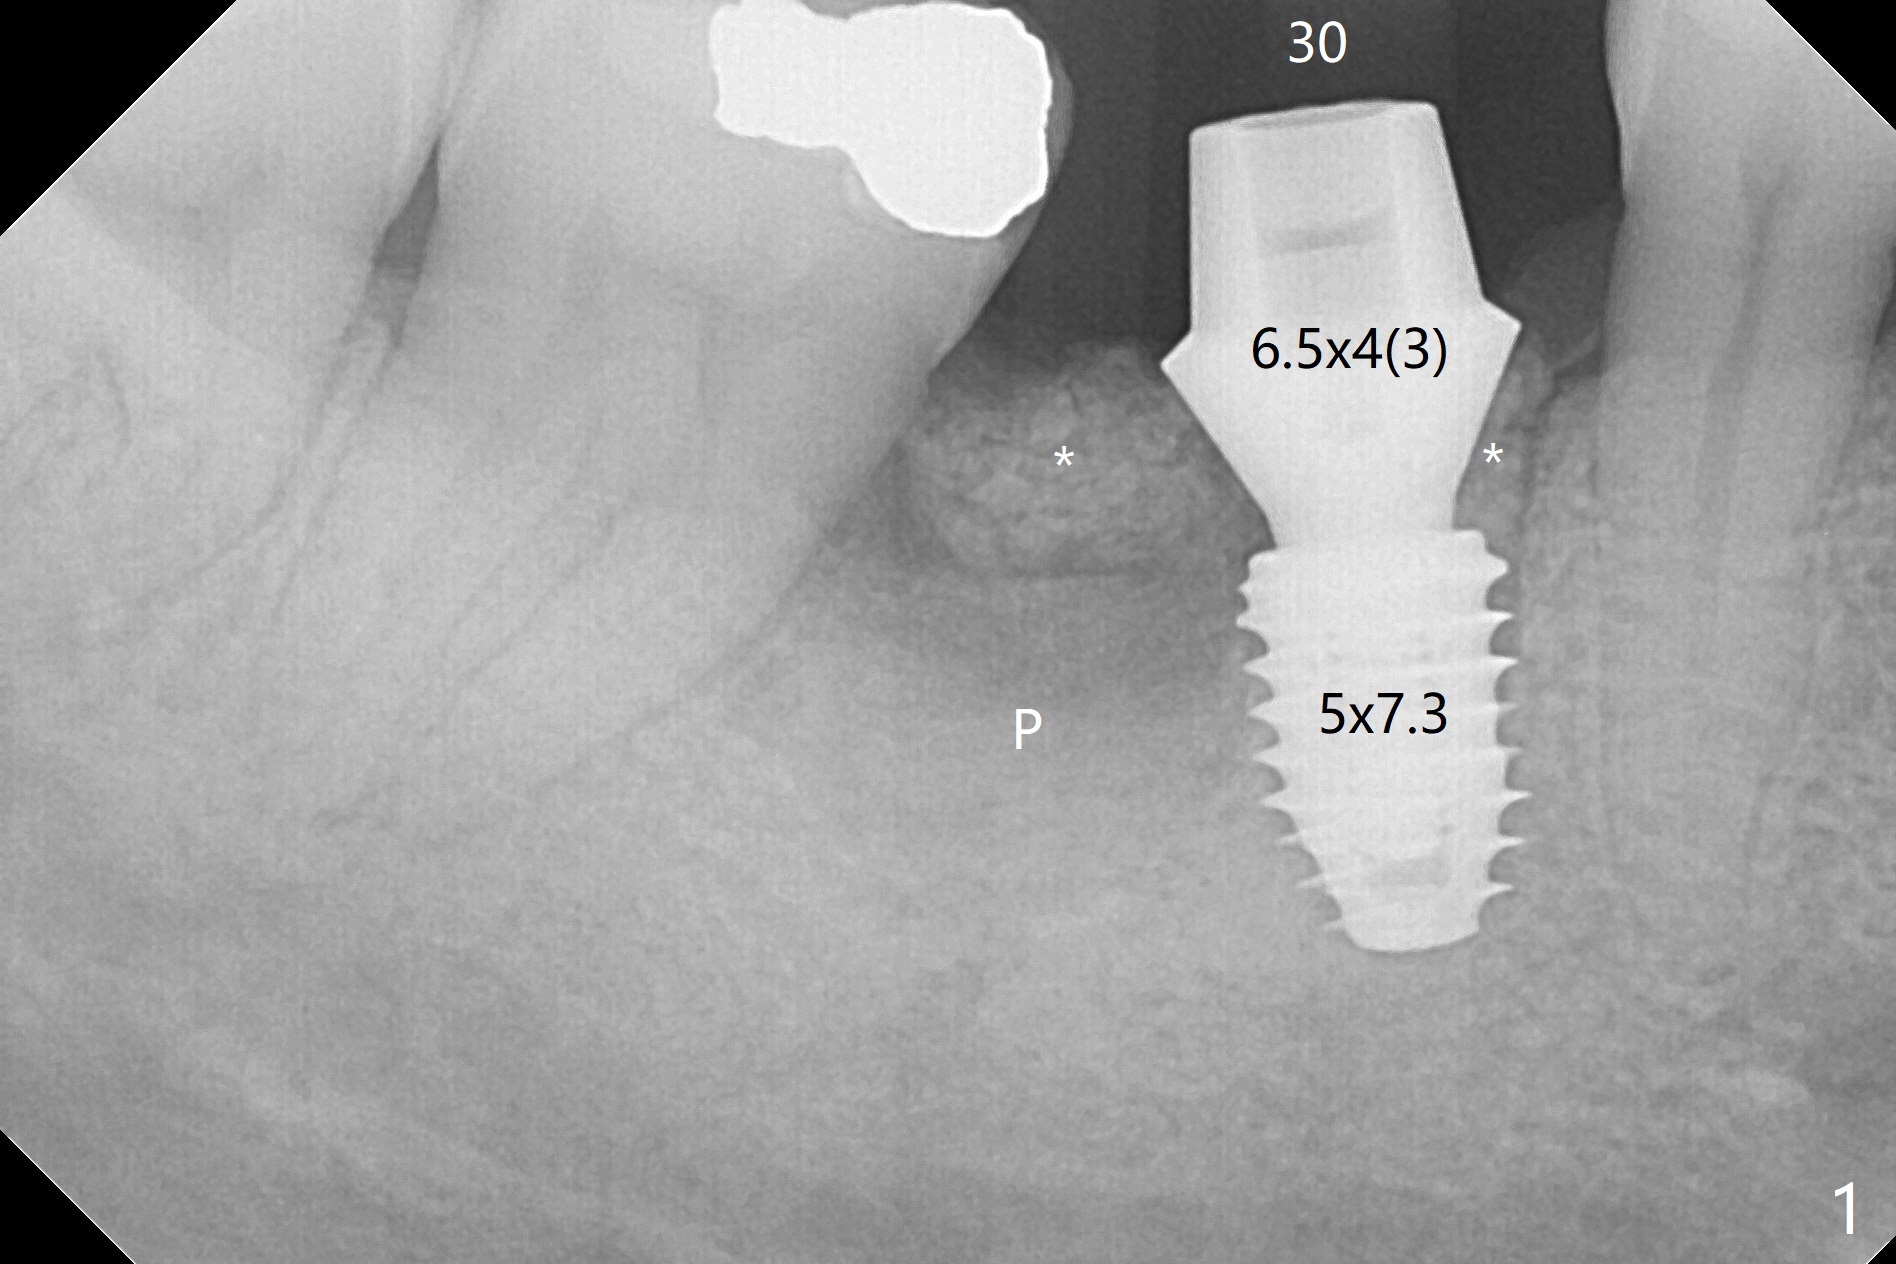

In spite of severe bone loss and 1.86 mm remaining bone after extraction of the tooth #30, a 5x7.3 mm implant achieves insertion torque of 35 Ncm with an immediate provisional (Fig.1). Periodontal dressing is applied for additional fixation of the bone graft (*) and Osteogen plug (P). Although the implant is placed in the mesial socket, the coronal end of the abutment is in the middle of the edentulous area. The patient is extremely pleased with no pain surgery. There is no postop paresthesia. The periodontal dressing (Fig.2 D) remains in place and buccal to the temporary crown (T) 10 days postop. When the former is removed, there is a gap between the margin of the provisional and that of the gingiva (Fig.3 between arrow and arrowhead), suggesting that the latter has shrunk postop. If there were no periodontal dressing, some of bone graft may have been lost. The distal socket heals when the immediate provisional is removed for revision 5 weeks postop (Fig.4). With gingival retraction cords, the abutment margin is prepared 2 months postop, particularly distal, to reduce food impaction in the future. If there is no abutment screw loosening with final restoration, it suggests that computer designed trajectory is acceptable. The implant plateau seems to be covered by the bone 4.5 months postop (Fig.5). In fact the mesiobuccal margin of the abutment is close to the corresponding crestal bone. The gingiva looks healthy 5 months postop (immediately before cementation, Fig.6), although MO amalgam of the tooth #31 is breaking down (*). Return to Lower Molar Immediate Implant, Prevent Molar Periimplantitis (Protocols, Table), Trajectory Xin Wei, DDS, PhD, MS 1st edition 04/17/2019, last revision 09/14/2019